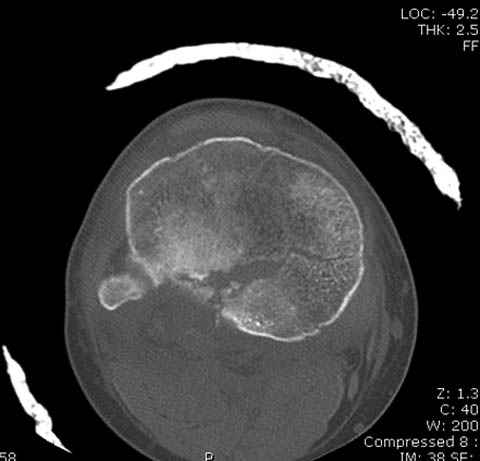

Здесь как раз тот случай, когда результат зависит не только от мастерства хирурга, но и от наличия современных методов исследования. Например, КТ которая поможет рассчитать направления шурупов и установку импланта. Кроме этого, поможет определиться с доступом.

На представленных предоперационных срезах КТ огромный задне-медиальный фрагмент расположен больше кзади, чем медиально. Для планирования, кроме поперечных срезов, надо ориентироваться на корональные срезы, которые укажут топографию верхушки медиального фрагмента.

Доступ к медиальной стороне задний или медиальный, через pes или в пространстве между medial gastroc мышцы.